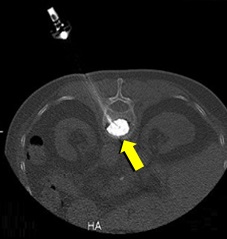

[非血管系IVR] 圧迫骨折(胸椎) 手術:経皮的椎体形成術(PVP)

CT画像

セメント注入中